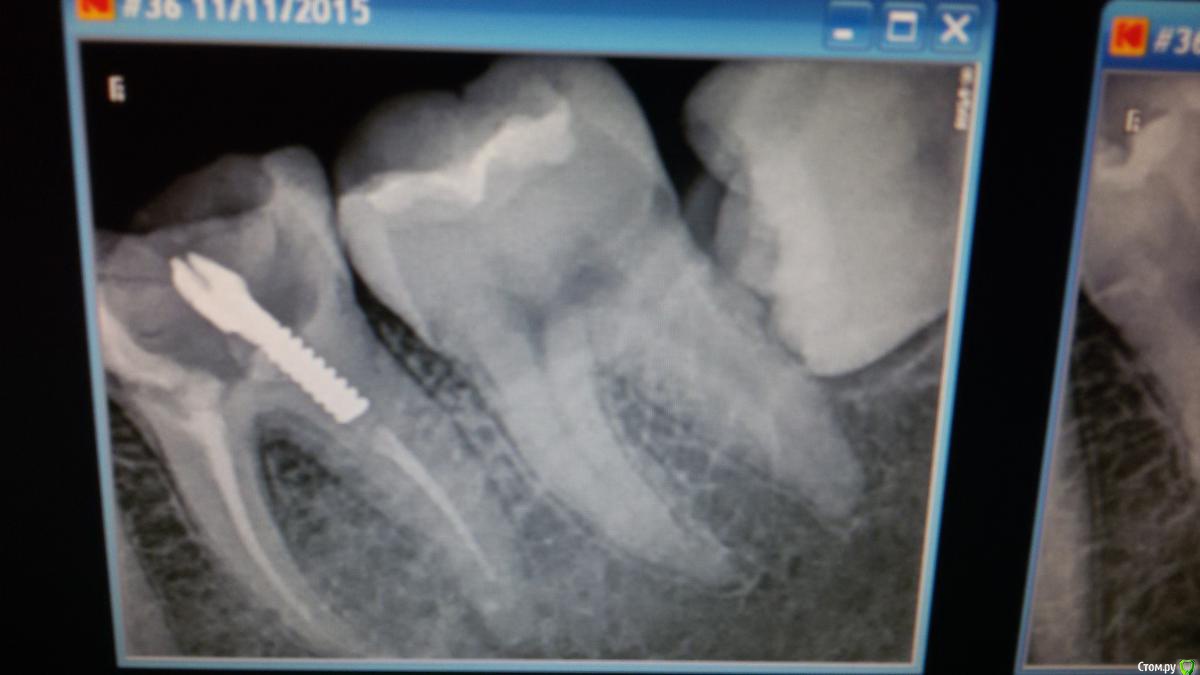

Mashelya Опубликовано 14 апреля, 2016 Поделиться Опубликовано 14 апреля, 2016 Всем добрый день! Пациентка 33 года. Пришла ко мне в ноябре 2015. Беременность 32 недели. Болит зуб 36. Снимок 1. Ноющая боль усиливается при накусывании. Перкуссия 36 положительная. Сделали снимок- штифт в дистальном канале. Расширение периодонтальной щели. Ну что делать- зуб болит, распломбировали, помыли почистили. Отделяемого не было. Два раза она ко мне приходила с интервалом 2недели. Мыли и каласепт. Договорились долечить после родов. Она больше не приходила, не звонила. Приходит ко мне дней 10 назад. Снимок 2. Говорит, за 2дня до этого скололась временная пломба, и, так как ко мне ехать далеко, а дома маленький ребенок, сходила в ближайшую стоматологию с целью поменять пломбу. Там ей естественно все вскрыли, снова чистили, мыли каналы. И вот теперь снова все болит. Ну в каналах, к слову, ничего не было(пасты имею в виду), ни на снимке, ни визуально. Снова все моем. Оставляю каласепт. Пациентка говорит, что прям вот уже все прошло, ничего не болит, уже жаждит вкладку и коронку. Я предлагаю сделать КЛКТ, так как в принципе вижу зуб в третий раз и то через полгода. И вот что видим. На медиальном корне большой воспалительный процесс. Дистальный тоже не в порядке. Перелечивание с вкладкой и коронкой примерно 25 т.р. Как считаете, это перспективно? Ведь процесс не на верхушке а между корнями, вот что меня смущает. Не хочу обнадежить человека, если потом все равно имплантация через пару лет. Ссылка на комментарий